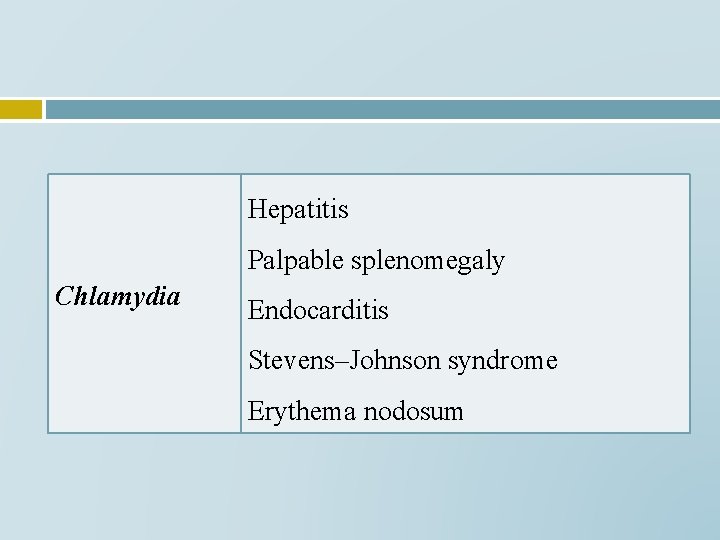

Hepatitis Palpable splenomegaly Chlamydia Endocarditis Stevens–Johnson syndrome Erythema nodosum